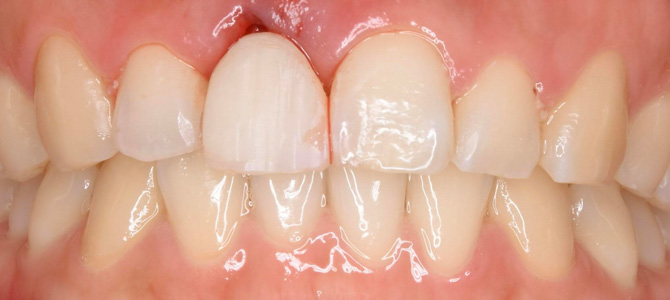

初診時口腔内写真。

左上の前歯が抜け落ちています。

初診時の翌日にキレイな仮歯が入りました。

治療開始から3ヶ月後に、天然歯と全く違いが分からないレベルのセラミック歯が入りました。